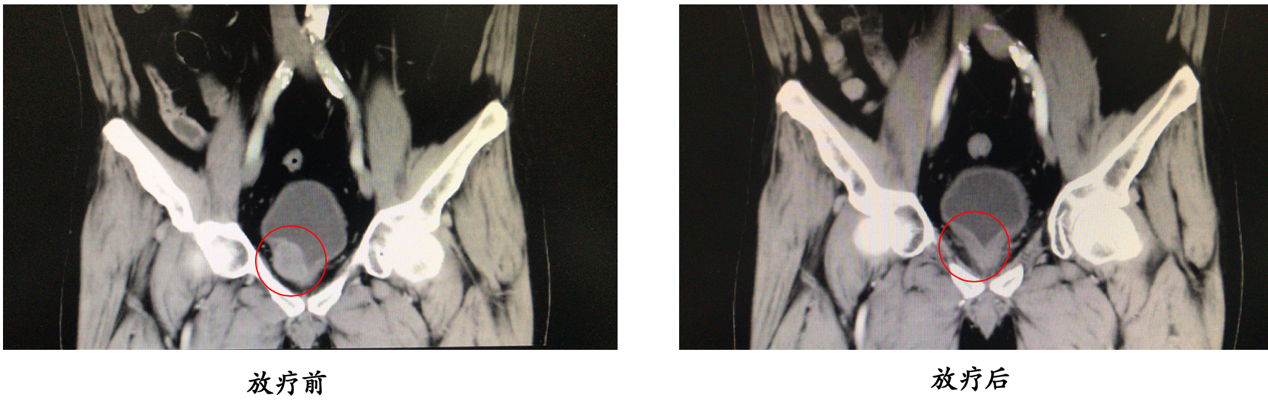

面对膀胱癌的高发病率、高恶性度以及高死亡率,为使中国膀胱癌患者获得更为先进以及更优化的膀胱癌治疗手段,北京大学第三医院成立了膀胱癌多学科诊疗团队(multidisciplinary therapy, MDT),以综合治疗为手段,提高膀胱癌患者的整体治疗效果和治疗后的生活质量。以此为契机,膀胱癌MDT团队已经开展了多项保留膀胱治疗项目,并申请了国际临床试验(NCT03756207),将国际先进的治疗方案引入国内,并且结合临床经验,不断改进和更新,为中国膀胱癌患者提供更优化的治疗方案。经过不断的治疗努力,已经有一批患者在我院接受了保留膀胱治疗,并且效果良好。

图3:典型病例介绍